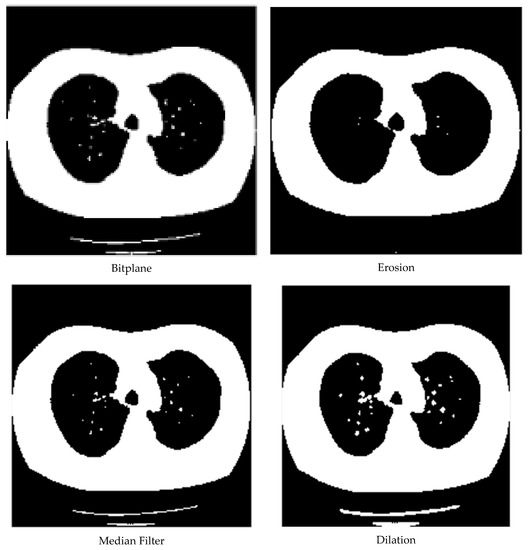

3.1. Data Pre-Processing